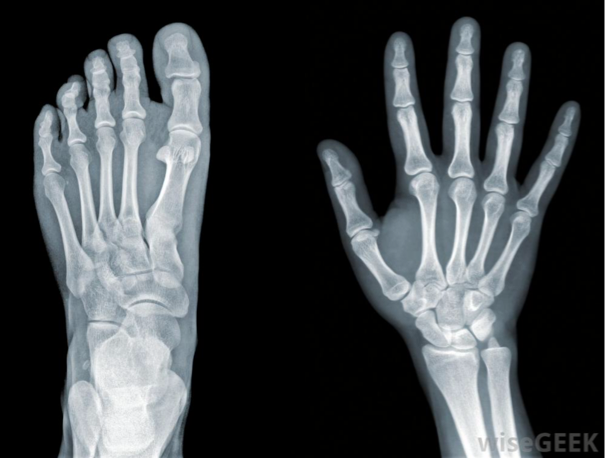

Extra Bones

10% of the human population have at least one extra bone in their bodies., but only 2% of that 10% discover they have one due to an injury. This is not a problem, but it is the body's way of connecting a loose tendon to existing bone.